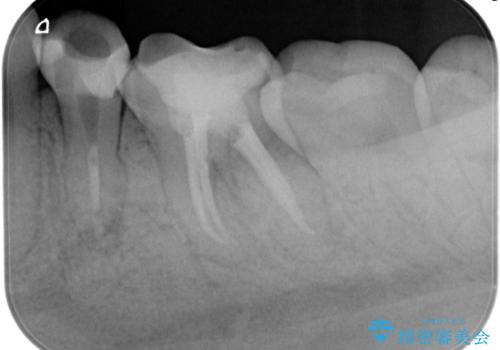

精密根管治療。大臼歯イニシャルケース

- 奥歯がズキズキ痛いことを主訴に来院されました。

検査の結果、診断を症候性不可逆性歯髄炎、症候性根尖性歯周炎とし抜髄を行っております。

根管充填はCWCTにて行なっております。

根管形成はマルテンサイト相を有するNi-Tiロータリーファイル(NEX MS)使用。